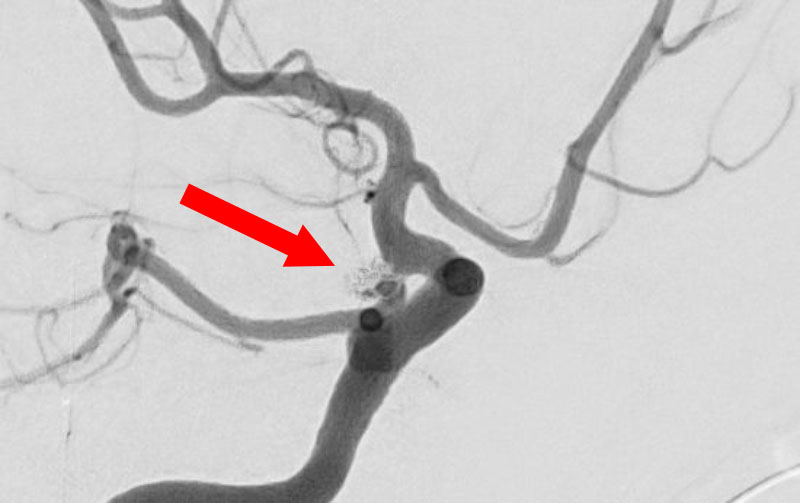

No.1631 手術後